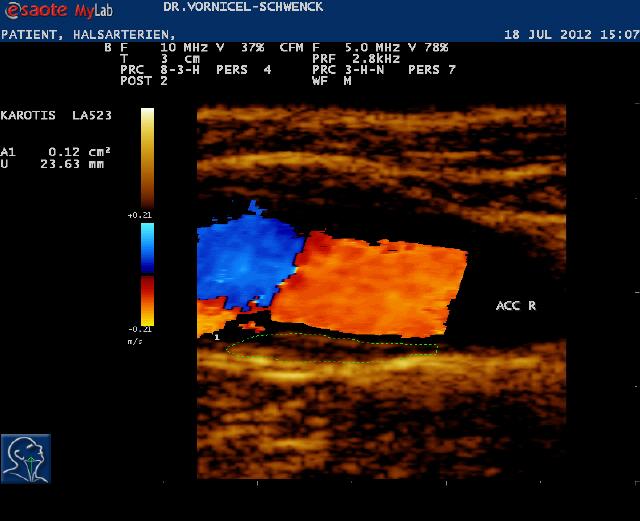

Sonografie (Sonographie), auch Echografie oder umgangssprachlich Ultraschall genannt, ist die Anwendung von Ultraschall als bildgebendes Verfahren zur Untersuchung von organischem Gewebe in der Medizin. Ein Sonogramm ist ein Bild, das mit Hilfe der Sonografie erstellt wurde.

Ein wesentlicher Vorteil liegt in der Unschädlichkeit der eingesetzten Schallwellen. Die Anwendung von Ultraschall ist eine sehr sichere Methode für die Bildgebung.

Die Sonografie ist das wichtigste Verfahren bei der Differentialdiagnose eines Akuten Abdomens, bei Gallensteinen oder bei der Beurteilung von Gefäßen und deren Durchlässigkeit. Sie wird standardmäßig zur Untersuchung der Schilddrüse, des Herzens und der Bauchorgane benutzt. Alle wasserhaltigen, blutreichen Organe sind für den Ultraschall gut untersuchbar. Manche Organe sind im Normalzustand nur schwierig, im krankhaft vergrößerten Zustand dagegen ganz gut erkennbar (Blinddarm, Harnleiter, Nebennieren).